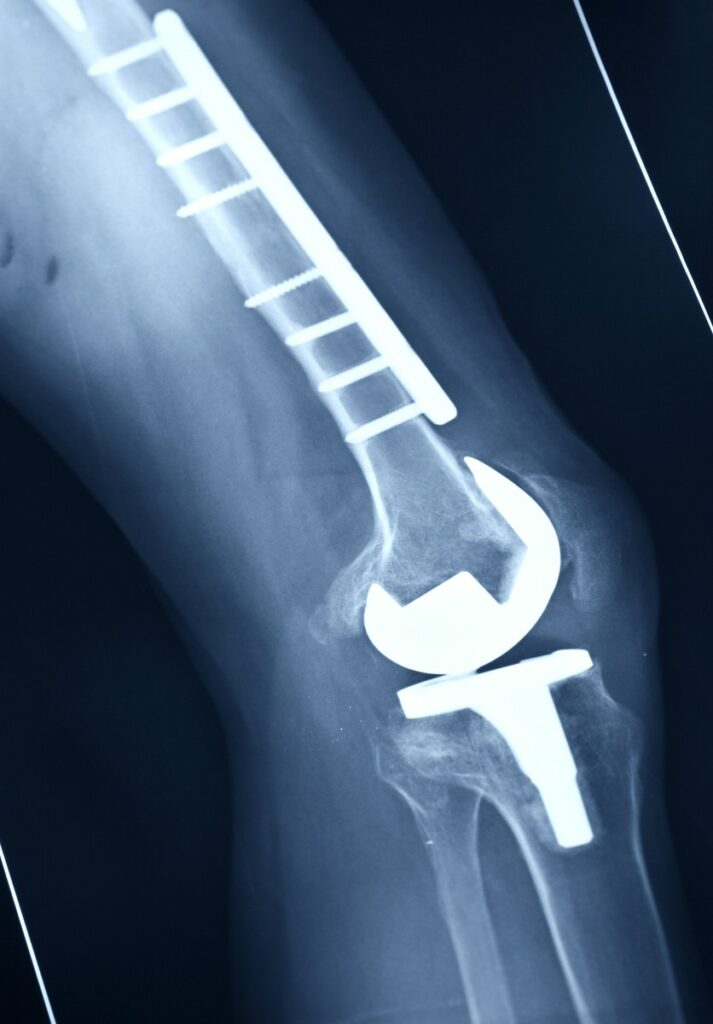

Powikłania po osteotomii mogą obejmować różne problemy zdrowotne, które występują po przeprowadzeniu zabiegu. Najczęściej zgłaszanymi trudnościami są infekcje, krwawienia oraz problemy z gojeniem się kości. Warto zwrócić uwagę na czynniki ryzyka, które mogą zwiększać prawdopodobieństwo wystąpienia tych komplikacji. Należą do nich m. in. choroby współistniejące pacjenta, takie jak cukrzyca czy otyłość, które mogą utrudniać proces gojenia. Ponadto zastosowanie odpowiednich metod chirurgicznych oraz technik zespolenia kości może wpłynąć na zmniejszenie ryzyka powikłań. W przypadku tego rodzaju operacji istotne jest również monitorowanie stanu zdrowia pacjenta po zabiegu oraz wczesne rozpoznawanie ewentualnych problemów. Dzięki temu możliwe jest szybkie wdrożenie odpowiednich działań terapeutycznych i uniknięcie dalszych komplikacji. Współpraca z doświadczonymi specjalistami może znacząco poprawić wyniki leczenia oraz jakość życia pacjentów po tym zabiegu.

Powikłania po osteotomii mogą obejmować różne problemy związane zarówno ze stawami, jak i tkankami miękkimi. Wśród najczęstszych komplikacji wymienia się infekcje, krwawienia oraz uszkodzenia nerwów. Długoterminowe skutki operacji mogą wpłynąć na funkcjonowanie pacjentów, prowadząc do bólu czy ograniczenia ruchomości. Dlatego istotne jest monitorowanie stanu zdrowia po zabiegu oraz odpowiednia rehabilitacja. Proces ten odgrywa kluczową rolę w powrocie do pełnej sprawności, pomagając uniknąć problemów związanych z powikłaniami po osteotomii. Należy również pamiętać o różnicach w występowaniu komplikacji po różnych typach osteotomii. Niektóre metody mogą wiązać się z większym ryzykiem problemów zdrowotnych, dlatego przed podjęciem decyzji o przeprowadzeniu zabiegu warto skonsultować się ze specjalistą i omówić wszystkie dostępne opcje leczenia. Dzięki temu pacjent będzie mógł dokonać świadomego wyboru oraz zminimalizować ryzyko wystąpienia niepożądanych efektów ubocznych.